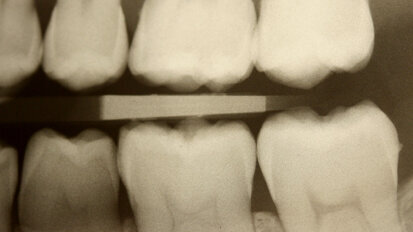

Rehabilitace Straumann